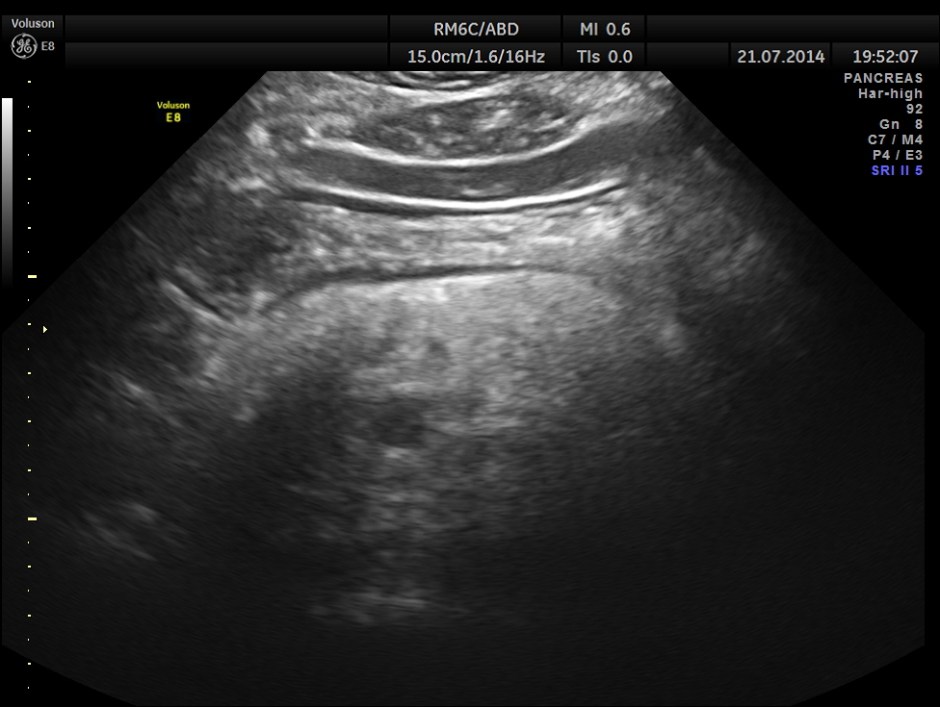

The following pictures show the pancreas.

Pancreatic duct is dilated prominently.

Pancreatic duct dilated.- 12.9 mms.

Pancreatic calculi are seen.